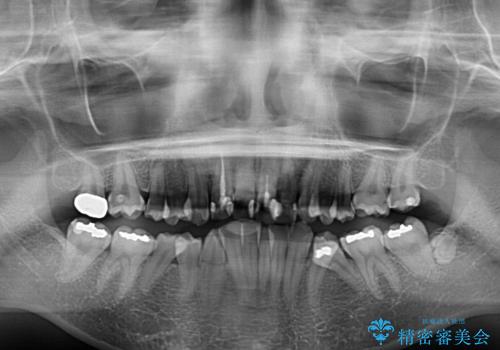

- 内側に倒れ込んだ歯や下の前歯が隠れてしまうほどの咬み合わせを改善したいとのことで来院された患者様です。

下顎の叢生を解消するために抜歯が必要であり、奥歯の咬み合わせや口元の印象から、上顎も同様に抜歯と判断し、上下左右の第1小臼歯4本抜歯してワイヤー装置にて矯正治療を行うこととしました。